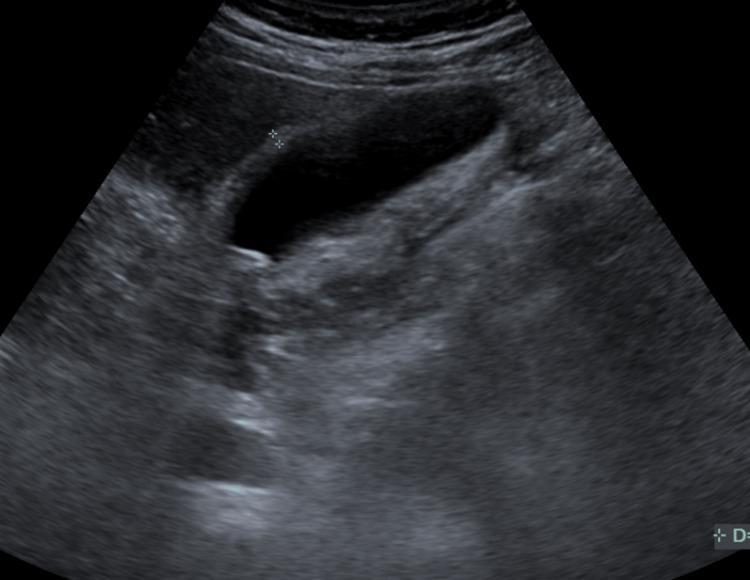

Acute pancreatitis is a common inflammatory disorder of the pancreas. While commonly caused by gallstones, alcohol use, and idiopathic causes, drug-induced acute pancreatitis (DIAP) is an often overlooked etiology that demands careful medication review and clinical vigilance. This case report describes a 72-year-old male patient with a history of hypertension and coronary artery disease who presented with severe epigastric pain radiating to the back, elevated lipase levels, and imaging findings consistent with acute pancreatitis. After excluding common causes such as gallstones, alcohol use, and hypertriglyceridemia, hydrochlorothiazide (HCTZ) was identified as the likely trigger. Discontinuation of hydrochlorothiazide led to clinical improvement and resolution of laboratory abnormalities. This case highlights the importance of considering drug-induced acute pancreatitis, particularly in patients with comorbidities who present with unexplained acute pancreatitis due to their pharmacological therapy.